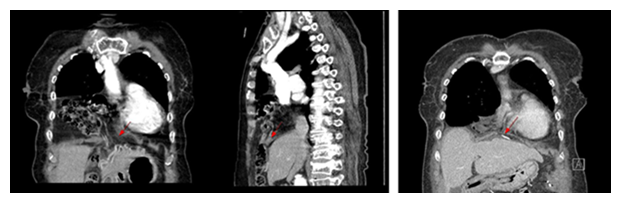

The most common presenting symptom was gastrointestinal discomfort (5/11, 45.5%), followed by chest pain (2/11, 18.2%), respiratory distress (2/11, 18.2%), and back pain (2/11, 18.2%); three patients (27.3%) were asymptomatic at diagnosis (Table 2). Computed tomography (CT) established the preoperative diagnosis in all patients, and routine postoperative CT was obtained on postoperative day (POD) 5 (POD 6 for the Bochdalek case) (Figures 4-6).

- Bochdalek hernia ; Pre-OP CT

- Post-OP CT (POD #6)